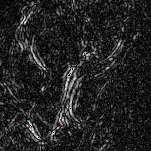

The rapid and accurate direct multi-frame interpolation method for Digital Subtraction Angiography (DSA) images is crucial for reducing radiation and providing real-time assistance to physicians for precise diagnostics and treatment. DSA images contain complex vascular structures and various motions. Applying natural scene Video Frame Interpolation (VFI) methods results in motion artifacts, structural dissipation, and blurriness. Recently, MoSt-DSA has specifically addressed these issues for the first time and achieved SOTA results. However, MoSt-DSA's focus on real-time performance leads to insufficient suppression of high-frequency noise and incomplete filtering of low-frequency noise in the generated images. To address these issues within the same computational time scale, we propose GaraMoSt. Specifically, we optimize the network pipeline with a parallel design and propose a module named MG-MSFE. MG-MSFE extracts frame-relative motion and structural features at various granularities in a fully convolutional parallel manner and supports independent, flexible adjustment of context-aware granularity at different scales, thus enhancing computational efficiency and accuracy. Extensive experiments demonstrate that GaraMoSt achieves the SOTA performance in accuracy, robustness, visual effects, and noise suppression, comprehensively surpassing MoSt-DSA and other natural scene VFI methods. The code and models are available at https://github.com/ZyoungXu/GaraMoSt.